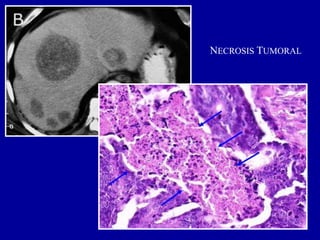

NECROSIS TUMORAL

1. NECROSIS POR COAGULACIÓN

 tumores de crecimiento rápido

 Necrosis estructurada: no se pierde la arquitectura normal del órgano o

tejido donde asienta, dibujándose los contornos de los componentes

tisulares.

 Las células aparecen sin núcleo (cariolisis) y forman masas homogéneas

y eosinófilas.